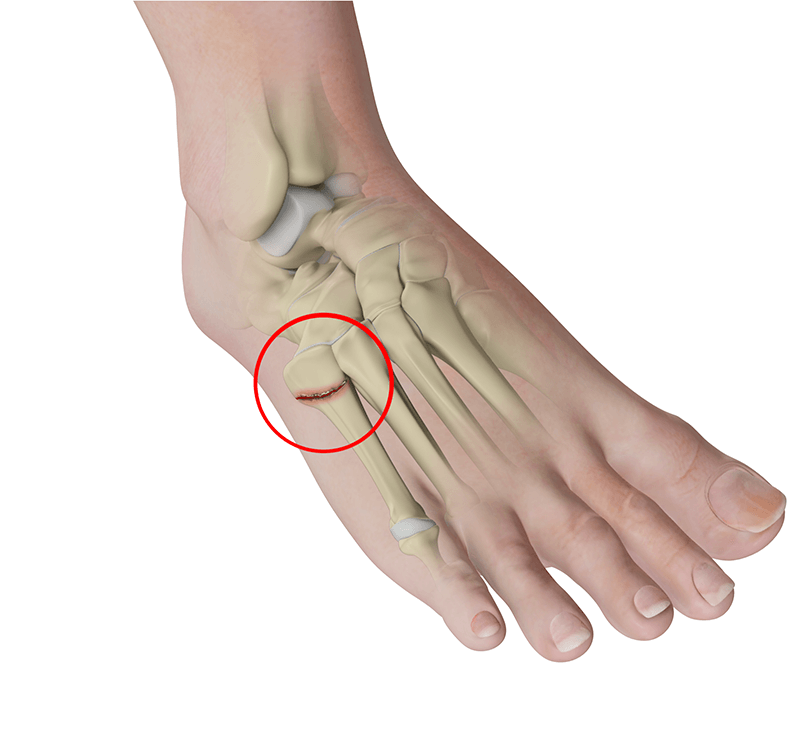

Immediate swelling and pain over the base of the fifth metatarsal. High nonunion rate and course of healing is unpredictable. Two fractures in the name.

Jones Fracture or Dancers Fracture